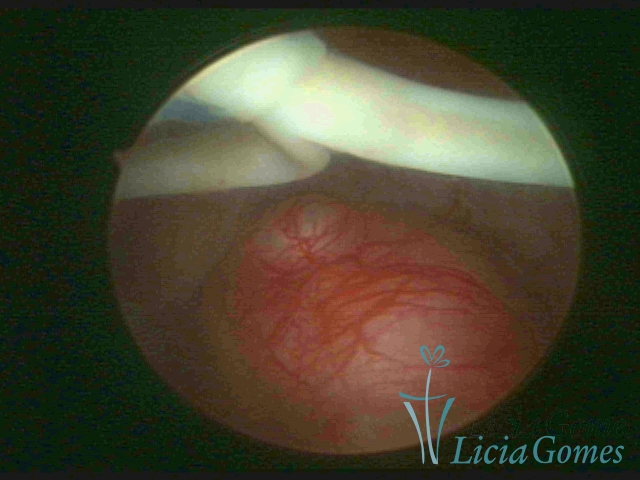

Dispositivo Mirena® e um mioma submucoso